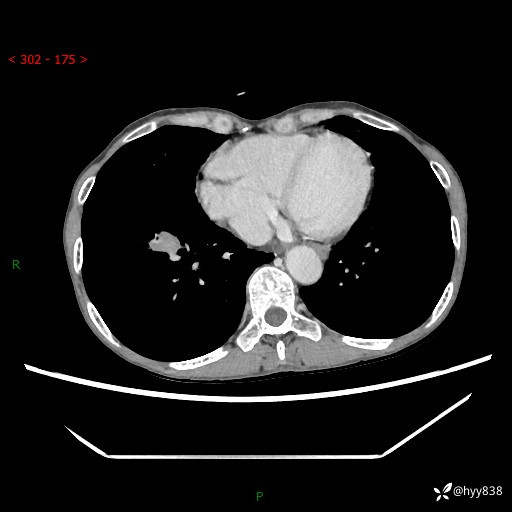

69岁/女,发现肺占位3天余。精彩好病例,请慧诊---(有结果)

【患者信息】:69岁/女

【主诉】:发现肺占位3天余

【现病史及既往史】:患者3天余前因既往肺气肿复查胸部CT发现“右肺下叶结节、双肺多发结节、双肺门及纵膈淋巴结增大”,平素偶有咳白色粘液痰,下肢乏力,无明显低热、盗汗、咯血、胸痛、喘气等不适,今为求明显结节性质遂来我院门诊就诊,门诊以“孤立性肺结节”收治入院。 起病以来,患者精神饮食睡眠一般,大小便正常,体力无明细变化,体重近年来较前下降。

【检查】:胸部CT增强